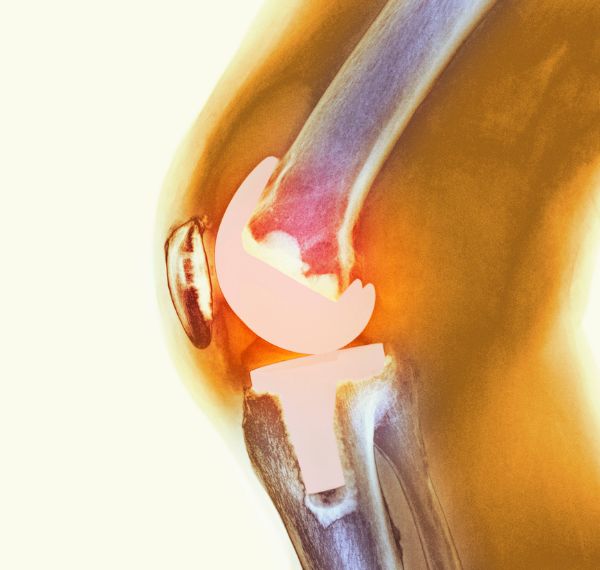

Total Knee Replacement (TKR)

Replaces damaged knee joints with artificial implants for lasting relief.

Unilateral Knee Replacement

Replacement of a damaged or diseased knee joint on one side (single knee) with an artificial implant.